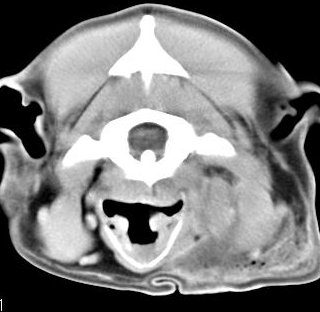

imágenes de TC en el perro | ||||||||||

ejemplo de imágenes de TC en el perro. Nótese la celulitis en la región parotídea izquierda | ||||||||||